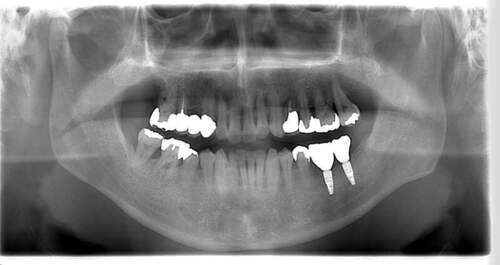

インプラント治療の症例4

レントゲン写真

- Befor

- After

| 年齢 | 50代・男性 |

|---|---|

| 主訴 | 部位:左下6番7番 主訴:左下奥歯腫れて痛い。 |

| 治療内容 | 左下6番抜歯、左下6番7番骨造成、インプラント埋入 |

| 治療費 | 合計:1,232,000円 ・内訳 診断料:55,000円 サージカルガイド2本:66,000円 GBR:110,000円×2本 埋入料:165,000円×2本 静脈内鎮静麻酔:77,000円 2次OPE:22,000円×2本 仮歯:55,000円×2本 上部構造(フルジルコニア):165,000円×2本 (2023年1月現在) |

| 治療期間 | 約8ヶ月 |

| リスク・副作用 | リスク・副作用 |

| 治療方針 | 元々支台歯に負荷がかかりやすいとされている延長ブリッジを抜歯し、1本単体でしっかりかめるようにインプラントを2本埋入した。骨吸収も進んでいたため、※GBR法で骨造成を同時に行った。 治療と並行して、全顎的な歯周病治療も行い、今後は歯周病が進行しないよう、こまめにメンテナンスに通っていただく。 |

| 特記事項 | ※1 GBR・・・骨再生誘導法。骨の高さや厚みを人工骨や人工膜などを使用し再生する方法 |

| 担当者所見 | 6番は歯根分割された被せ物が7番の欠損部との延長ブリッジとされており、強い咬合と歯周病も相まって負荷がかかり動揺し、歯として機能しなくなったため、抜歯となった。 |